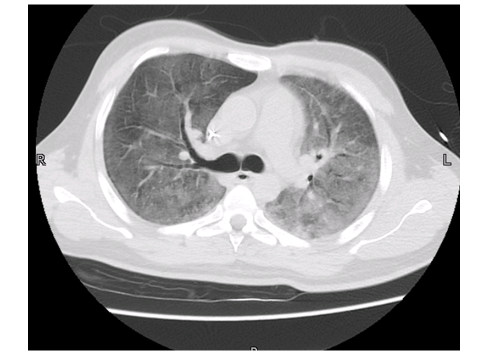

A 23-year-old student with chest pain for 2 months. What is the diagnosis?

Question Image